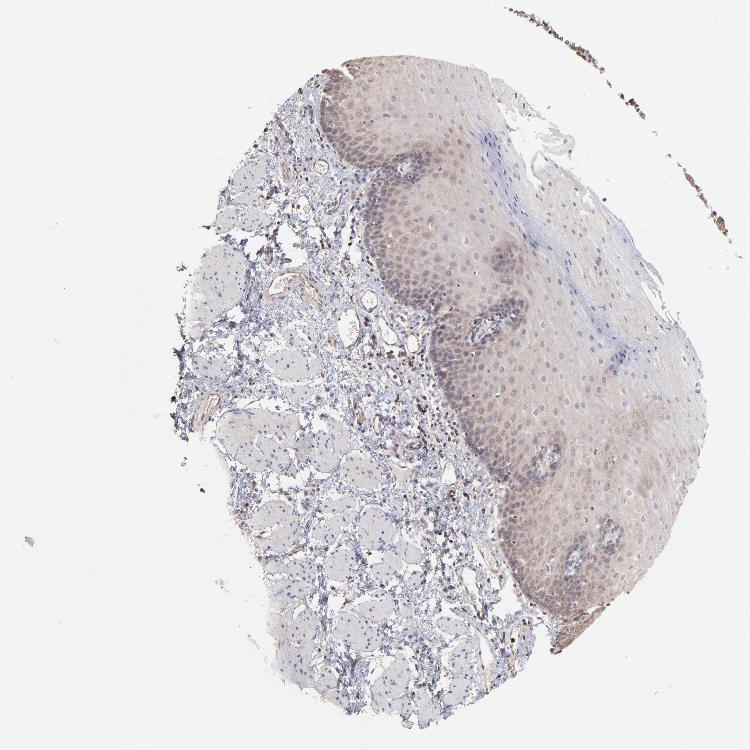

ESOPHAGUS - Antibody stainingi

Antibody staining in the annotated cell types in the current human tissue is reported as not detected, low, medium, or high, based on conventional immunohistochemistry profiling in selected tissues. This score is based on the combination of the staining intensity and fraction of stained cells.

Each image is clickable and will lead to virtual microscopy that enables deeper exploration of all samples and also displays staining intensity scores, fraction scores and subcellular localization as well as patient and tissue information for each sample.

Antibody HPA051993Antibody CAB003835

Squamous epithelial cells MediumLow